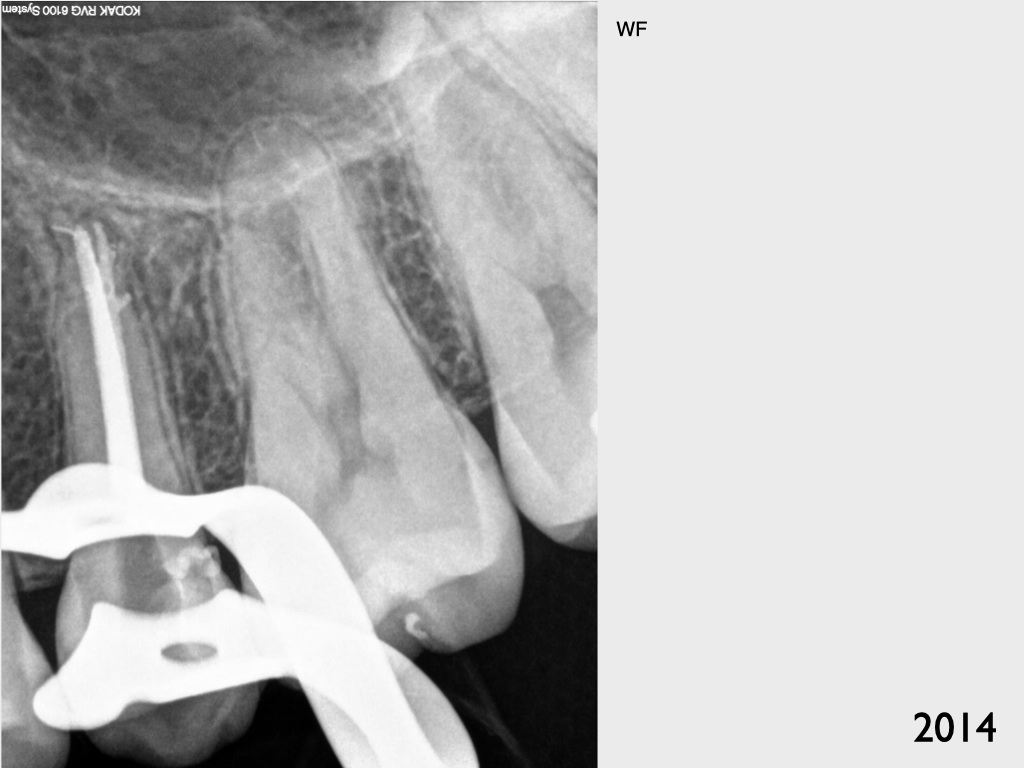

Recall 7 Jahre